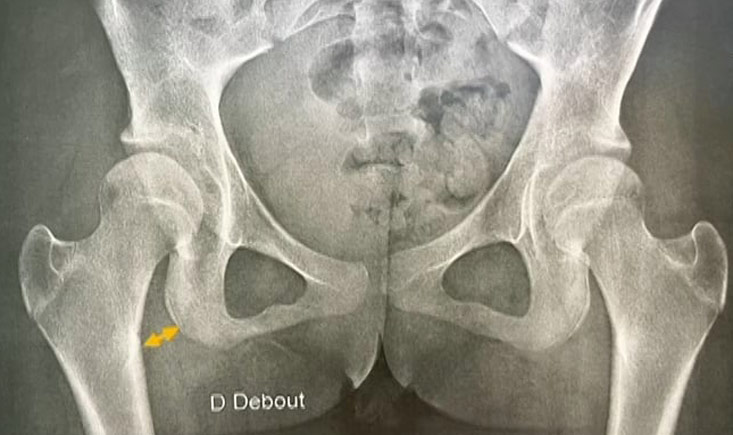

Hip preservation: Patient stratification- a bad candidate for preservation but a good candidate for TJA?

Discover the key to selecting the right patients for conservative surgery or total hip arthroplasty. Explore real-life cases, see how 40+ sports patients recover after hip scope, and get actionable tips for starting your hip preservation practice.

Complementing his clinical practice, his research interests centre around Optimisation of arthroscopic management of femoroacetabular impingement. In particular, he has been working on disease stratification of FAI using novel imaging techniques, better pre-operative planning tools using dynamic analysis of the hip and optimisation of arthroscopic management of FAI via precision surgery using navigation to improve outcomes.